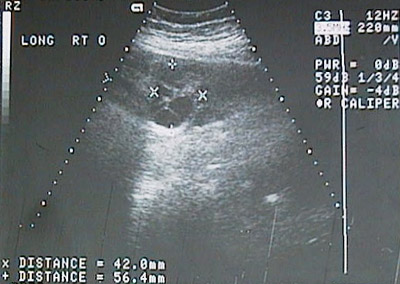

In this ultrasound view, a cystic ovary is present because the very high beta-HCG level has resulted in the development of ovarian theca lutein cysts.